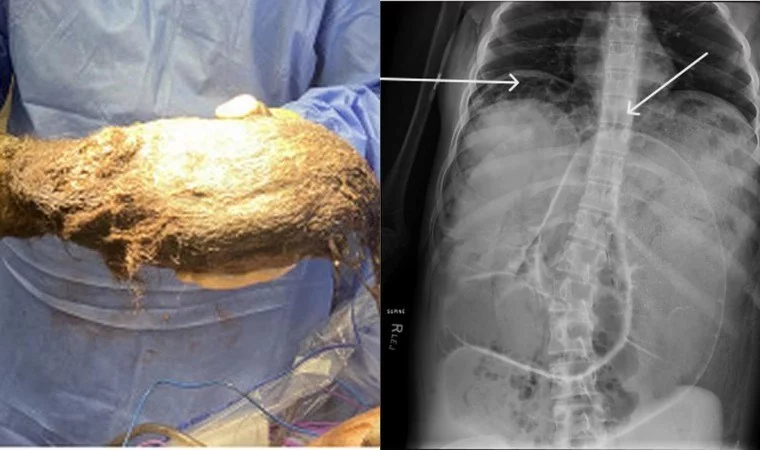

News24.az bildirir ki,  qızın mədəsindən 2,5 qramlıq tük kürəsi çıxarılıb. Həkimlər bunun "Rapunzel sindromu" olduğunu deyiblər.

Şoka düşən həkimlər mürəkkəb prosedurdan sonra qızın mədəsindən çəkisi 2468 qram olan tük kürəsini çıxarıblar.